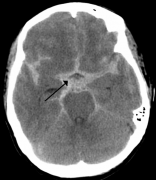

顱內(nèi)動(dòng)脈瘤,又稱腦動(dòng)脈瘤,是一種腦血管疾病,由于大腦動(dòng)脈或靜脈管壁薄弱,導(dǎo)致血管局部擴(kuò)張或膨脹。后循環(huán)(基底動(dòng)脈、椎動(dòng)脈和后交通動(dòng)脈)的動(dòng)脈瘤有較高的破裂風(fēng)險(xiǎn)。基底...

Q:腦動(dòng)靜脈畸形出血率和死亡率風(fēng)險(xiǎn)高嗎? A:AVM的總體年出血率約2-4%,但這不適用于全部的AVM,部分AVM潛在的解剖和血流動(dòng)力學(xué)相關(guān)特性使其更具有出血傾向。 促使出血的兩類主要...

腦動(dòng)脈瘤 破裂屬于疾病嗎?中國大約有4000萬腦動(dòng)脈瘤患者,每年大約1%有破裂風(fēng)險(xiǎn),也就是說每年大概會(huì)新增40萬腦動(dòng)脈瘤破裂患者,而破裂出血可能導(dǎo)致腦損傷,甚至有40%的死亡風(fēng)...